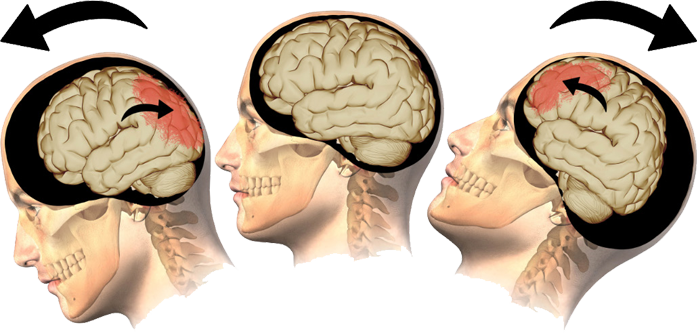

This part of the brain is responsible for behavioral output (social and cognitive behaviors), as well as body movement. Some of the many behaviors and functions of the human brain include: inhibition; behavior initiation and self-regulation; abstract reasoning; attention and working memory; executive functioning (multitasking, organizing, etc.); and movement (muscles involved in speech, facial expressions, etc.).This brain region is often affected by TBI from motor vehicle accidents, especially injuries caused by rapid acceleration-deceleration type events.

This part of the brain is responsible for behavioral output (social and cognitive behaviors), as well as body movement. Some of the many behaviors and functions of the human brain include: inhibition; behavior initiation and self-regulation; abstract reasoning; attention and working memory; executive functioning (multitasking, organizing, etc.); and movement (muscles involved in speech, facial expressions, etc.).This brain region is often affected by TBI from motor vehicle accidents, especially injuries caused by rapid acceleration-deceleration type events.

- Rapid acceleration-deceleration (though no direct impact is required, a restrained driver/passenger coming to a sudden halt causes the brain inside the skull to move and hit the skull wall with such force resulting in brain tissue damage)

Rapid Acceleration-Deceleration Injury

Falls are by far one of the most common causes of TBI with highest risk of injury at both ends of the age spectrum. Any force to the head may result in TBI. If you suspect that you have suffered from any form of TBI, please seek help from a medical professional immediately.